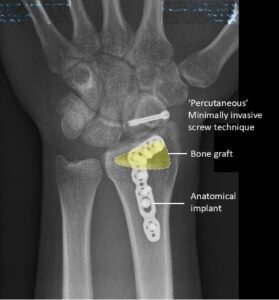

Figure 2: Knowledge of specialised techniques and implants improves outcomes. These implants do not require a second surgery for removal.

In complex or unusual fractures, standard plates and screws may not be enough. These cases may require customised surgical implants that fit the patient’s bone anatomy precisely.

Specialist wrist surgeons are trained to handle these situations – using techniques such as:

- Anatomically contoured plates for better bone alignment

- Fragment-specific fixation to stabilise small bone fragments

- Bone grafting when bone loss or severe comminution is present